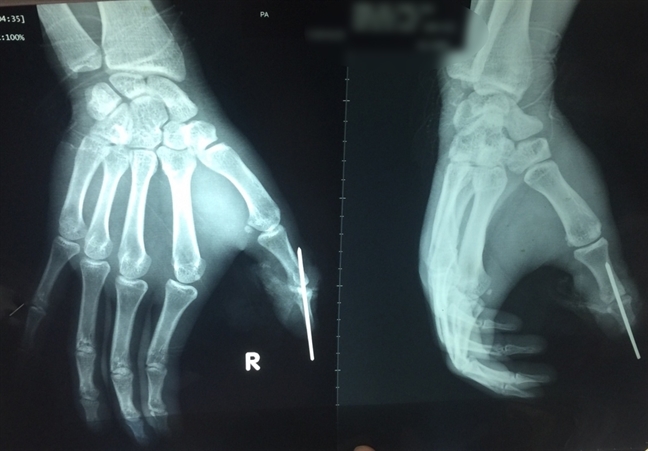

Ảnh chụp X-quang ngón tay được cứu sống. Ảnh:BSCC

Bác sĩ Ngọc Thạch người mổ chính ca ghép nối cho biết, ngón cái chiếm tỉ lệ 50% sức của 4 ngón tay còn lại. Chưa kể, mất ngón tay khiến bệnh nhân mặc cảm. Nhờ phần bị đứt lìa được bệnh viện tuyến trước vệ sinh, bảo quản tốt nên ca phẫu thuật thành công. Phần đứt lìa hiện tại được cứu sống và đang dần hồi phục tốt.